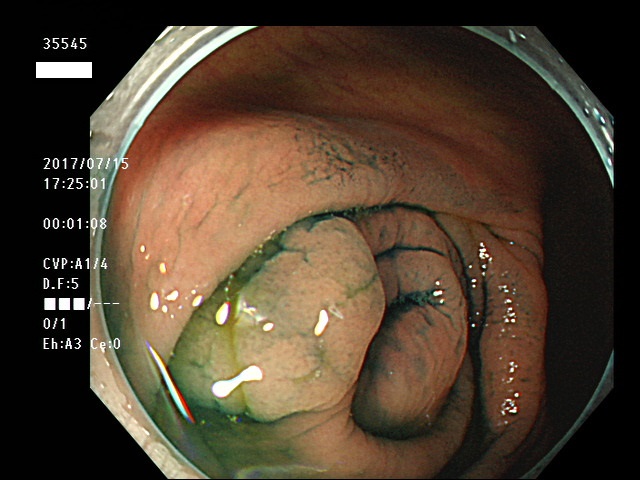

上記100名より抽出した平坦・陥凹型腺腫・SSAP(=癌化の危険が高いが見落としやすい病変)の内視鏡写真

35500 35501 35502 35506 35508 35509 35511 35514 35515 35516 35517 35520 35521 35522 35523 35524 35525 35526 35528 35532 35535 35536 35539 35542 35544 35545 35547 35548 35550 35553 35556 35559 35560 35561 35562 35563 35564 35567 35569 35570 35571 35578 35581 35584 35585 35587 35588 35589 35590 35592 35593 35594 35598 35599・・・・・の54名